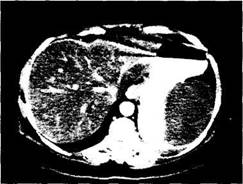

Clinic: tegumentele pot bomba, echimoza aparand tardiv de la 6-12 ore pana la 4 zile. Durerea este accentuata de palpare iar contractia musculaturii ficseaza tumefactia. Aceasta nu poate fi mobilizata in nici un sens (semnul Bouchacourt). Pentru confirmarea hematomului: punctie, echografie si, nu obligatoriu, CT (fig. 5).

Fig. 17. Hematom de flanc